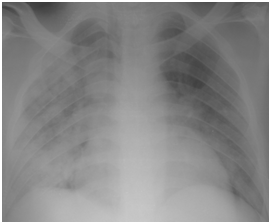

Graft failure occurred in 2 patients; one of them had already high serum creatinine at diagnosis (3mg/dl) and started dialysis 1year after H1N1 infection while the other has normal serum creatinine at diagnosis (1mg/dl) and was presented 1year later due to unexplained graft dysfunction. Some authors believe that influenza virus is capable of activating immunologic mechanisms leading to allograft rejection.9 The activation of such immunological mechanisms is related to production of interleukin -1, TNF, IL-6 and IL-8 during viral replication.10 The time interval for incidence of H1N1 infection started from the second half of December till the second half of January. Other series documented the incidence between the second half of July up to September in Asia (Singapore)8 while the largest number of confirmed cases of 2009 influenza A (H1N1) infection in North America occurred between March and July 2009.11 H1N1 infections has many complications in RTR including respiratory, cardiac and CNS sequences. However, the most common prescribed complication among RTR in the literature is respiratory complications. In one of early reports described 2 RTR that developed hypoxic respiratory failure and necessitated noninvasive ventilation12 while Singapore report described 2 mortalities among 10 cases of pneumonia.8 Other complications included H1N1 related myocarditis13 or encephalitis.14 In our series, only respiratory complications were encountered as previously mentioned. Our cases have excellent prognosis, most probably due to early initiation of oseltamivir therapy, doubling the dose and extension of the duration of treatment. Also temporary reduction of anti-proliferative drug may help RTR to recover early. Three cases of pneumonia showed inconclusive CXR while CT chest revealed bilateral infiltrates and this signifies the importance of CT chest in diagnosis of pneumonia in immune-compromised patients see Figure 3. Serial CXR was carried out to follow up lung recovery in cases of H1N1 pneumonia and it was correlated with the clinical response (Figure 4). The suspected number of RTR in December -2009 was 36 RTR which is double the number of suspected number in December-2010,this may be due to two facts; the first is vaccination with seasonal and novel H1N1 vaccine while the second is familiarity of criteria of diagnosis which reduced the number of suspected RTR.

Figure 3 Radiological diagnosis of H1N1 pneumonia in a 40-year-old female renal transplant recipient who suffered from fever and dyspnea of 2 days duration.